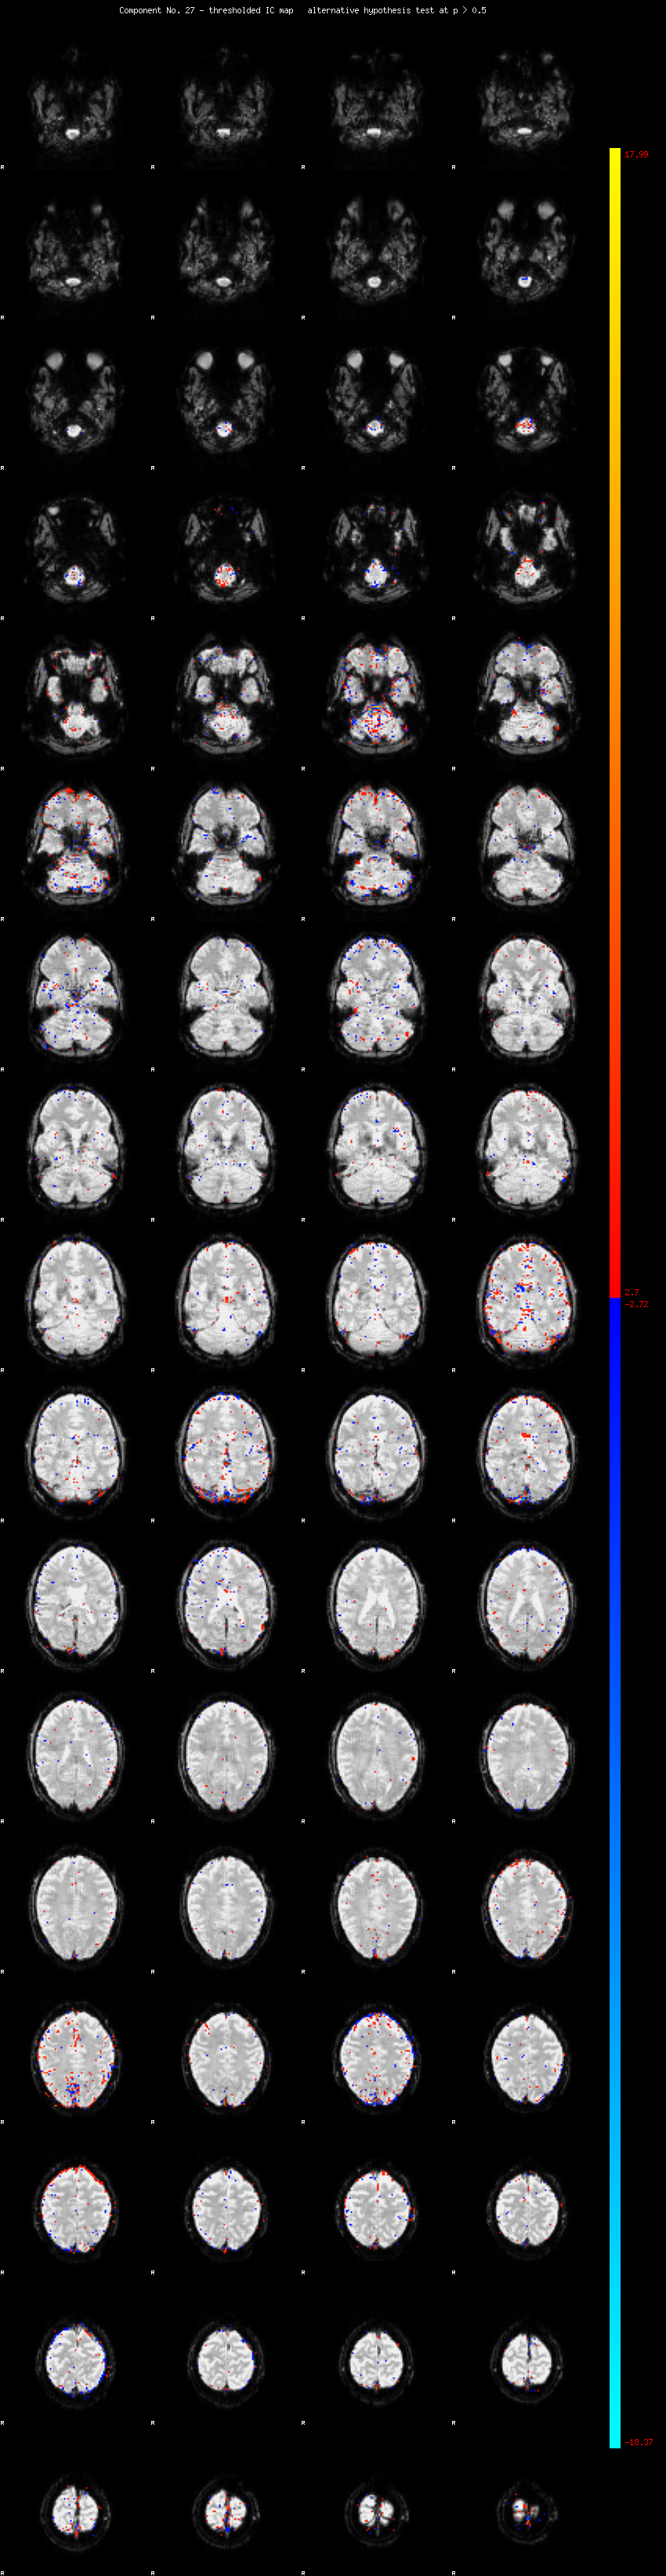

MELODIC Component 27

1.26 % of explained variance;     0.83 % of total variance